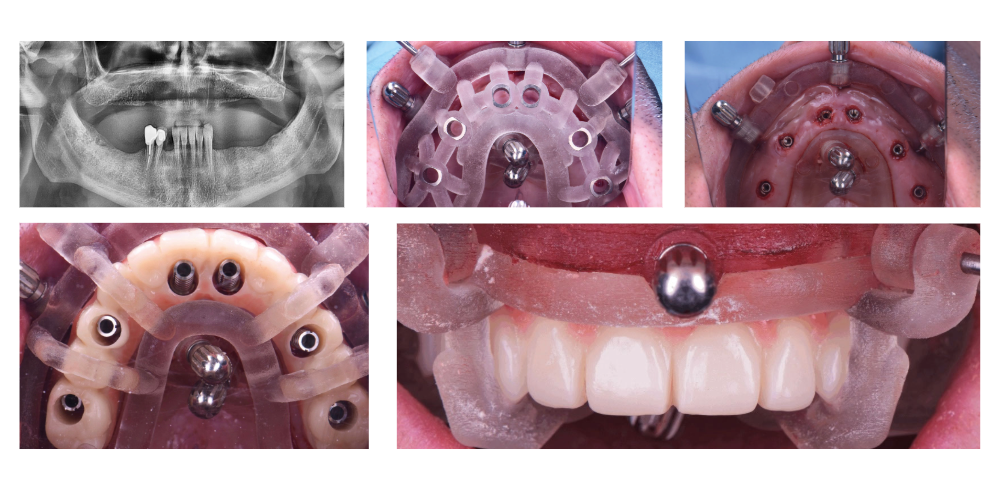

Le protocole OLYMP repose sur des guides à étages et un flux entièrement numérique. Il permet une prise en charge immédiate des patients édentés complets ou partiels, en conservant temporairement 3 dents (si le cas le permet) pour stabiliser le guide.

2. Chirurgie guidée

Extractions stratégiques, mise en place des implants, pose du bridge provisoire vissé.